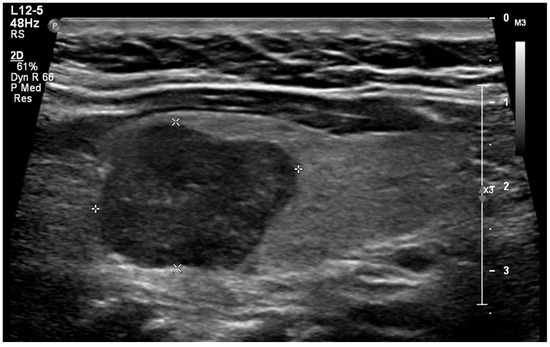

Thyroid nodules that exhibit lower echogenicity than the adjacent neck muscles are described as having a very hypoechoic or markedly hypoechoic appearance (Figure 4) [6,15,24]. Our study found a very hypoechoic appearance in 9.4% of malignant nodules compared to 0.6% of benign nodules. This characteristic was significantly associated with malignancy, yielding an OR of 13.3 (95% CI, 3.8 to 45.9), at p < 0.001. In a study involving 2255 nodules, of which 293 were malignant, Lee et al. discovered that for homogenously solid nodules, a marked hypoechoic or moderate hypoechoic appearance was associated with a significantly higher cancer risk (51.9 to 59.2% vs. 21.3%) compared to a mildly hypoechoic appearance (p < 0.001) [55]. In a multi-institution study involving 5601 nodules, of which 1089 were malignant, Lee et al. observed a malignancy risk of 64.8% in markedly hypoechoic nodules, 48.2% in moderately hypoechoic nodules, 23.5% in mildly hypoechoic nodules, and 8.7% in iso- or hyperechoic nodules (p < 0.001) [56]. Kim et al. examined the relationship between the histologic findings and nodule echogenicity, observing a trend of increasing fibrosis as the nodule echogenicity decreased [57]. These study findings may help explain the tendency for markedly hypoechoic nodules to be malignant, as fibrosis is an underlying feature in papillary cancer [57].

Figure 4. A malignant nodule with a very hypoechoic appearance.